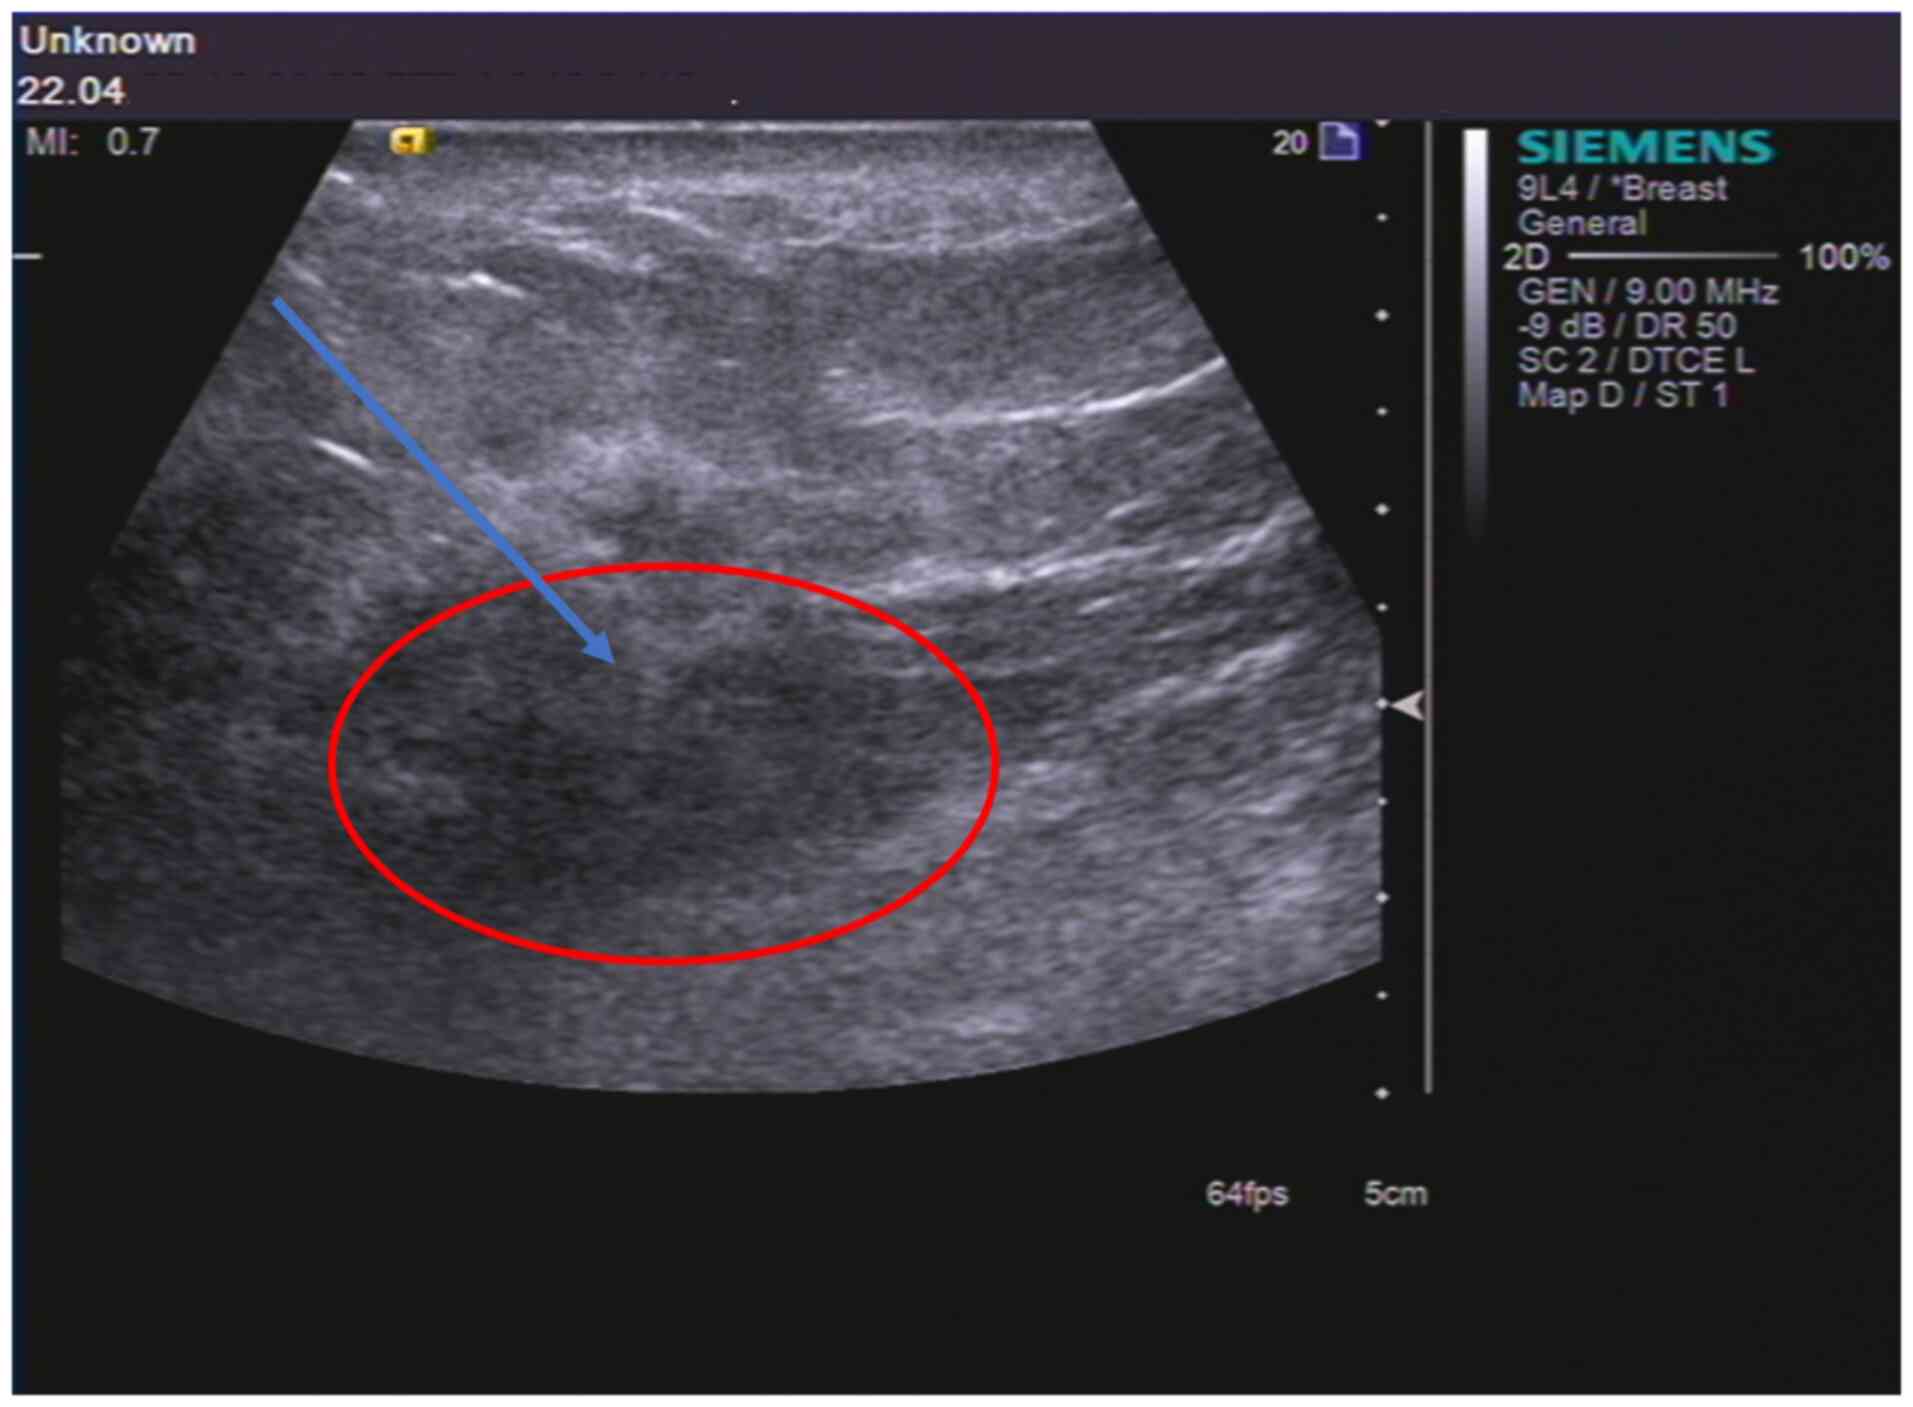

A total of 2 years after the radical resection

surgery, in April 2022, the patient was admitted to the Weifang

Second People's Hospital after experiencing redness and swelling of

the right breast mass for 1 month. Considering the medical history

of the patient, an ultrasound-guided aspiration biopsy of the right

breast mass was performed (Fig.

3). The pathology results revealed stage III inflammatory

breast carcinoma (T4N0M1) in the right breast (Fig. 1D). The patient was treated with